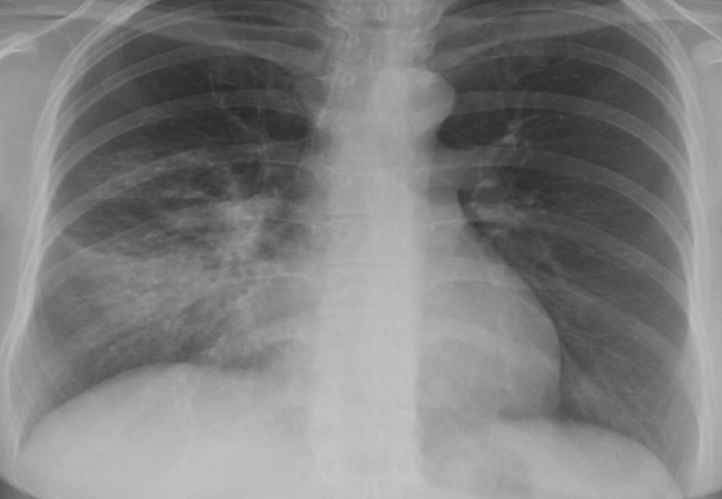

Right middle lobe pneumonia

pulmonary infeltrat

radio-opacity (air bronchograms)

Silhouette sign→loss of sharp border of the heart (on the right for this picture)

Right lower lobe pneumonia

Silhouette sign with right diaphragm (loss of sgarm border of right diaphragm)